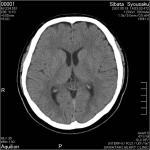

■頭部CT検査64列マルチスライスCT検査では、脳内出血やくも膜下出血、脳梗塞などがわかります。また、造影剤を使用することで、脳血管の立体的な三次元画像を作成する撮影が可能になり、 脳動脈瘤の診断ができます。